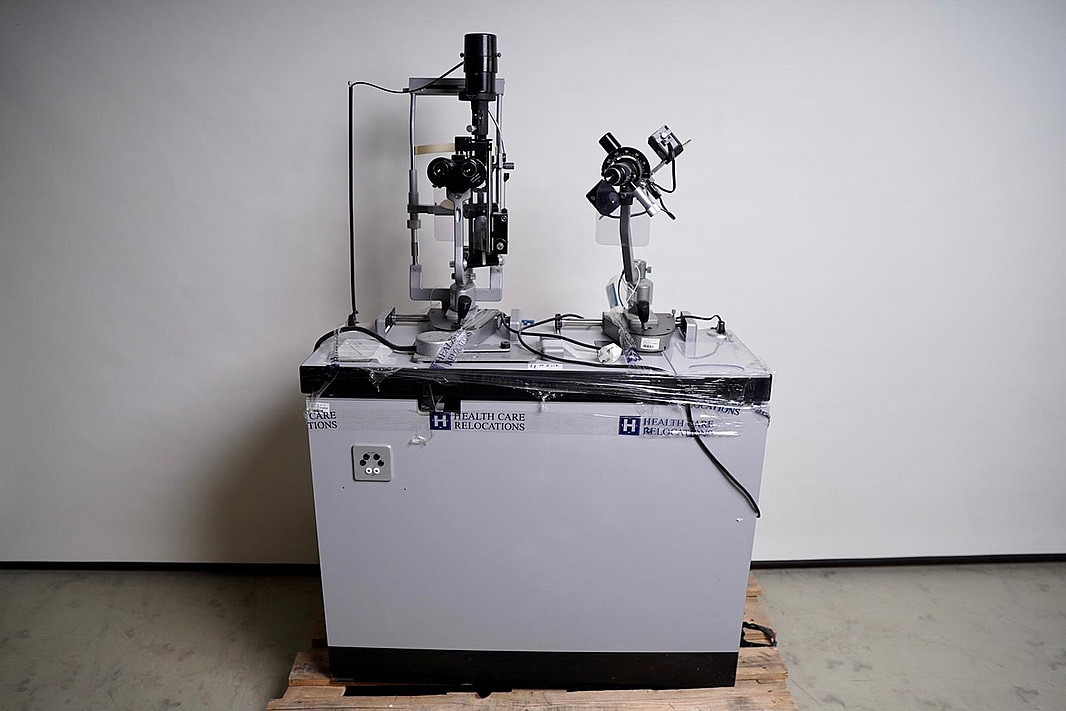

Optiker utrustning, undersökningsbord. Spaltlampa Haag-Streit 900.

Not allowedSpaltlampa Haag Streit 900

Mikroskåp

Dioptrien Haag Streit

Oftamologi/Ophtalmology

B90025223

M90025223

R90028569